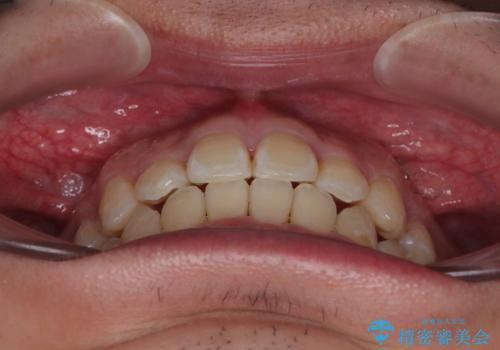

- 「歯並び全体のデコボコをきれいに整えたい」とのご希望で、20代男性の患者様が来院されました。

特に前歯部の叢生(歯の重なり)が強く、見た目だけでなく歯磨きのしにくさも気にされていました。

矯正中の見た目を気にされていたため、プラスチックブラケット+コーティングワイヤーを使用した、目立ちにくい審美矯正装置を選択しました。